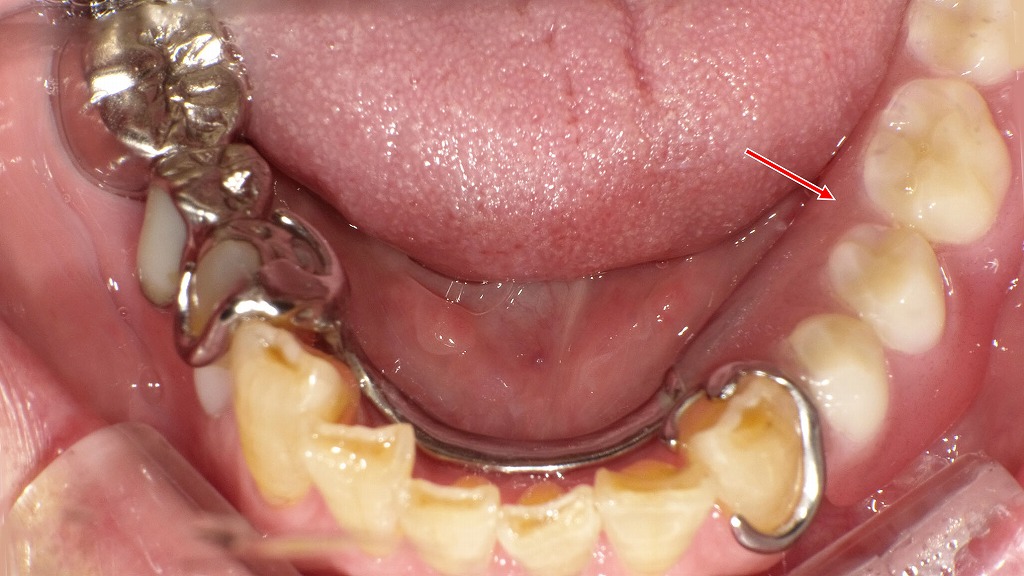

この写真は、**右上1番・2番・3番(中切歯・側切歯・犬歯)にメタルボンド冠(陶材焼付鋳造冠)**が装着されている症例です。矢印の部分に注目すると、いくつかの審美的および歯周的な問題が見られます。

🔍 観察ポイント

- 補綴物の種類:右上前歯3本にメタルボンド冠が装着されています。内側は金属フレーム、外側が陶材(セラミック)です。

- ブラックマージン(黒い境界線):歯と歯ぐきの境目に黒いラインが見られます。これは金属のフレームが歯肉退縮により露出しているためです。

- 歯肉退縮:右上1番・2番・3番で歯ぐきが下がり、根面(歯根表面)が露出しています。露出した部分は黒く変色しており、象牙質やセメント質の着色、または金属イオンの影響が考えられます。

- 審美的不調和:補綴物の色調と隣接天然歯のトーンが異なり、特に歯頸部の黒ずみが目立ちます。

⚠️ 想定される原因

- 経年的な歯肉退縮(加齢・ブラッシング圧・歯周病など)

- メタルボンドの金属フレームが光を透過しないため、歯肉が黒く見える(メタルシャドウ)

- 根面の露出による歯根象牙質の変色

- 金属成分(Ni・Crなど)が歯肉に沈着するメタルタトゥーの可能性もあり

💡 審美改善の選択肢

- オールセラミック冠(ジルコニア冠など)への置き換え

→ 金属を使用しないため、ブラックマージンや歯肉の黒ずみが改善されます。 - 歯肉移植(結合組織移植)による歯肉ラインの回復

→ 退縮部分をカバーし、より自然な歯肉形態を取り戻すことが可能。